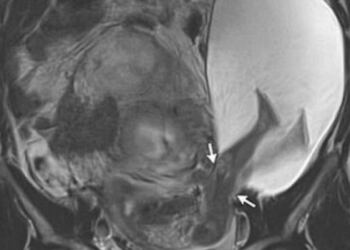

Αυτή η γυναίκα ήταν έγκυος για τα τελευταία 14 χρόνια…Η ιστορία της ξεκινάει από όταν ήταν 13 χρονών! Δεν θα το πιστεύετε!

Αυτή η γυναίκα είναι έγκυος για τα τελευταία 14 χρόνια και ξεκινάει ήδη από όταν ήταν 13 χρονών. Θα πάθετε ...